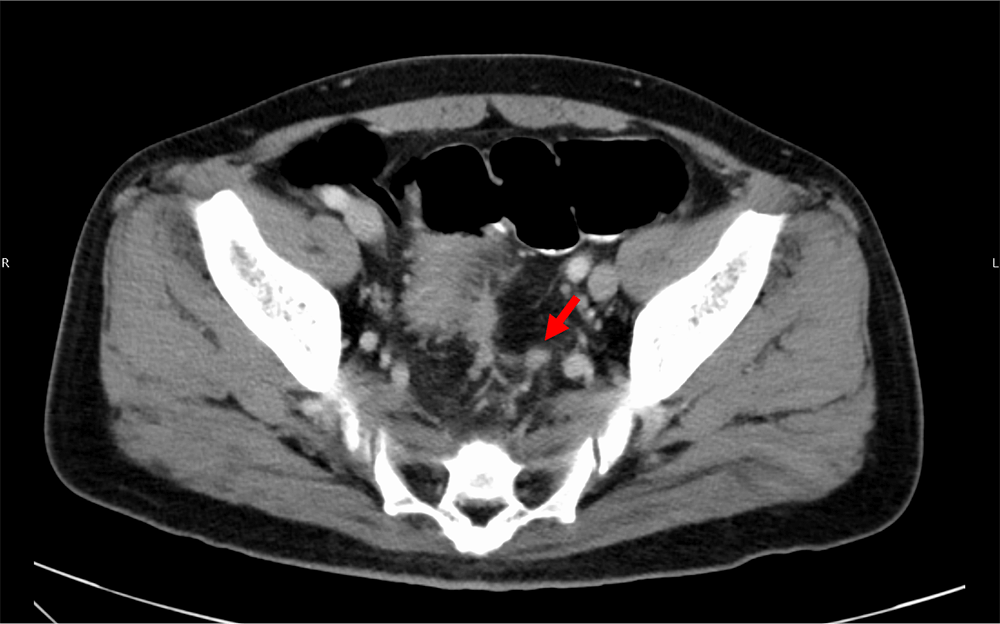

図5.門脈相(120kVp画像)、水平断

直腸左側に不定形の小結節が同定され、TD(矢印)が疑われる。

また直腸癌の予後不良因子である壁外静脈浸潤(EMVI)、tumor deposit(TD) の同定は重要であることが知られている。これらはMRIで診断されることが一般的であるが、造影CT検査でも指摘できることがある。仮想単色X線エネルギー画像(MonoE)は低エネルギー帯でヨードの造影効果が劇的に増加するため、病変や脈管の視認性が向上するので、検出能や診断確信度の向上に寄与すると考えられる。